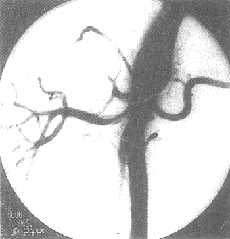

DSA的分辨率足够观察肾实质内直径小至1mm的血管,可诊断肾动脉病变达91.1%,有参考价值者6.6%,只2.3%影像不能作出诊断。DSA可以区分纤维肌肉发育不良、动脉粥样硬化、肾萎缩、肾动脉细小或肾动脉闭塞等症。在显影不够满意的病例,可因肾动脉开口处极度狭窄致使显影剂密度不足而影响肾内血管小分支的浓度,也可因动脉的重叠或心排血量不足所致。DSA可测出肾内血液分布的数值、灌注情况、积蓄功能以及廓清功能等,从而可准确地评估两肾的生理功能(图5、6)。

图5 腹主-肾动脉造影—DSA

图6 肾动脉造影—DSA